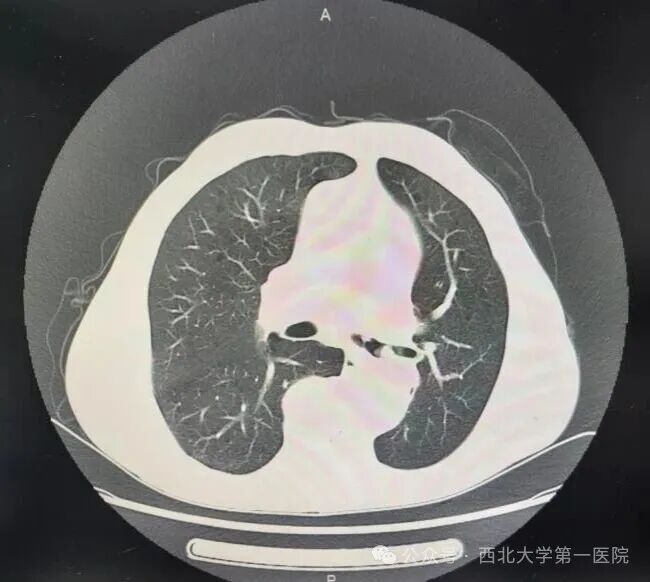

63岁的患者白某因“反复咳嗽、咳痰5月,痰中带血1月”来到西北大学第一医院就诊。患者有着长期吸烟史,还患有慢阻肺、高血压等基础疾病,身体状况不容乐观。入院后的胸部CT检查显示:左肺门占位,左主气管近乎完全堵塞,引发继发阻塞性肺炎,纵隔淋巴结肿大。如此复杂且危重的病情,让患者气道严重阻塞,不仅随时面临呼吸衰竭的风险,明确病理诊断也迫在眉睫。